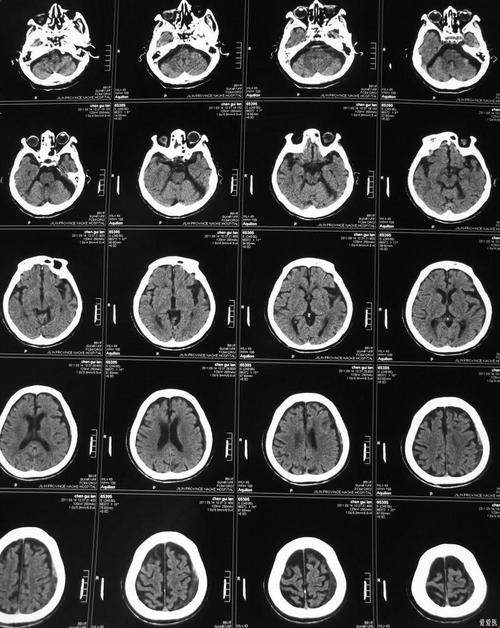

脑梗死的CT检查:基本原理和时间线

要理解怎么看,首先要明白CT在脑梗死不同时期的表现。

(图片来源网络,侵删)